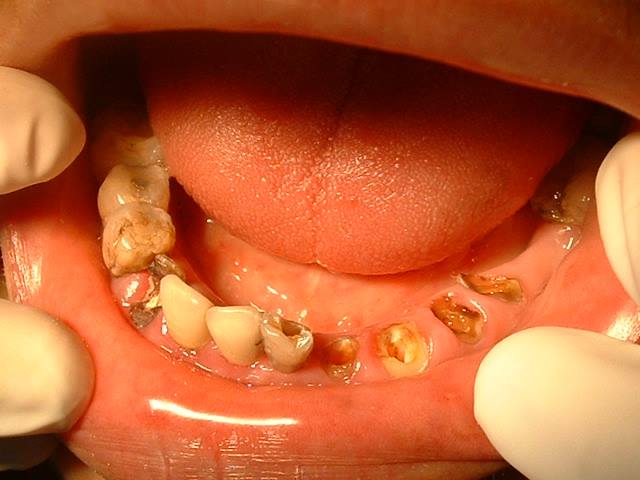

什么是根管治疗呢?所谓根管治疗,又称牙髓治疗,是治疗根尖周病或牙髓病最有效的技术。它通过清除根管内的坏死物质和发炎的牙髓,并进行适当的消毒,填充根管,以去除根管内的容物对根尖周围组织的不良刺激。根管治疗这种治疗方式不仅使牙齿得以保留,还能与拔牙术互补呢!一般牙齿因龋齿有洞,外部细菌侵入到牙髓腔,导致牙髓受到细菌感染而发炎的或是细菌侵入牙槽骨里,引起牙根尖周围组织发炎的,都需要进行根管治疗。

对根管治疗不了解的患者一听到这个名字就感到莫名的害怕。但想想,如果不做根管治疗,牙齿越往后越可能出现疼痛,阵痛,夜间痛,口臭等后果。牙齿如若病变到一定程度,后续也只能将其拔除,此时就算想做根管治疗,也无济于事。